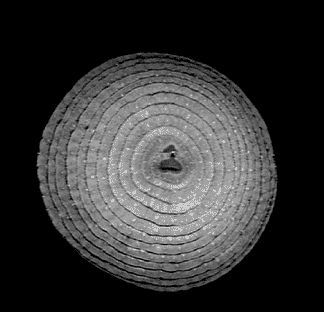

Quizás no sea lo más ortodoxo, pero no podemos negar su componente curioso y llamativo. Seguramente pocos nos imaginaríamos que una fruta de la pasión o la raíz de un apio tienen en su interior un aspecto muy similar al del cerebro. O que las fresas se parecen a un panal de miel. Aclaremos el misterio: esto ocurre cuando las frutas son observadas a través de una resonancia magnética.

Andy Ellison, técnico en resonancias magnéticas del Centro de Imágenes Biomédicas de la Escuela de Medicina de la Universidad de Boston, se ha propuesto enseñarnos de este modo cómo son las entrañas de las verduras y las frutas que comemos a diario. Para ello, ha utilizado la tecnología médica avanzada con la que trabaja para capturar las secciones transversales de estos alimentos, de la misma manera que cada día se hace con el cerebro humano, las rodillas o la columna.

El resultado, que recoge en su blog Inside Insides, son unas fascinantes imágenes y GIFs que nos muestran las frutas y las verduras desde otro punto de vista. Desde un interior tan llamativo y adictivo como lo pueden ser sus colores, formas y sus texturas. La colección es amplia y da para todo tipo de evocaciones, porque por el escáner de Ellison –en concreto, una Philips 3 Tesla MRI, explica– han pasado todo tipo de alimentos, desde los más comunes como las cebollas, los pimientos, los tomates o los plátanos, hasta lichis, la jaca (también conocida como jackfruit, uno de los frutos más grandes del mundo), la fruta del dragón o el kiwano (o pepino africano).